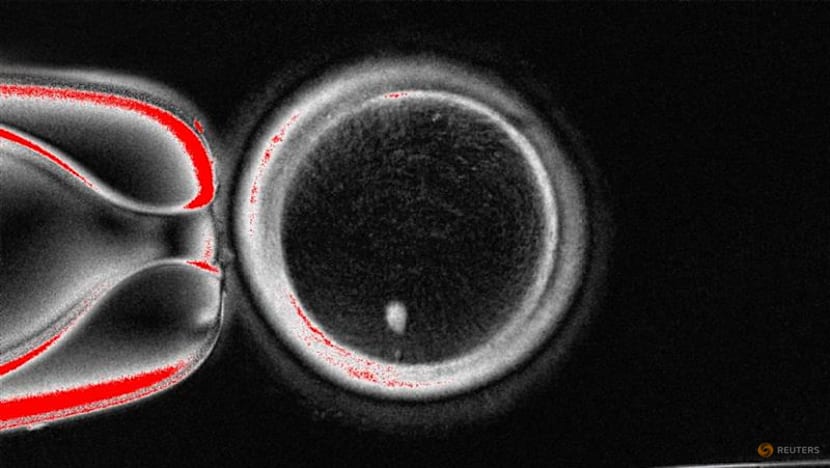

An image of an oocyte with a bright image of a skin cell nucleus before fertilization. via Oregon Health & Science University/REUTERS

The process, which would carry significant safety concerns, involves removing the nucleus from a woman's skin cell and inserting it into an egg, or oocyte, from which the nucleus has been removed, scientists detailed in Nature Communications.